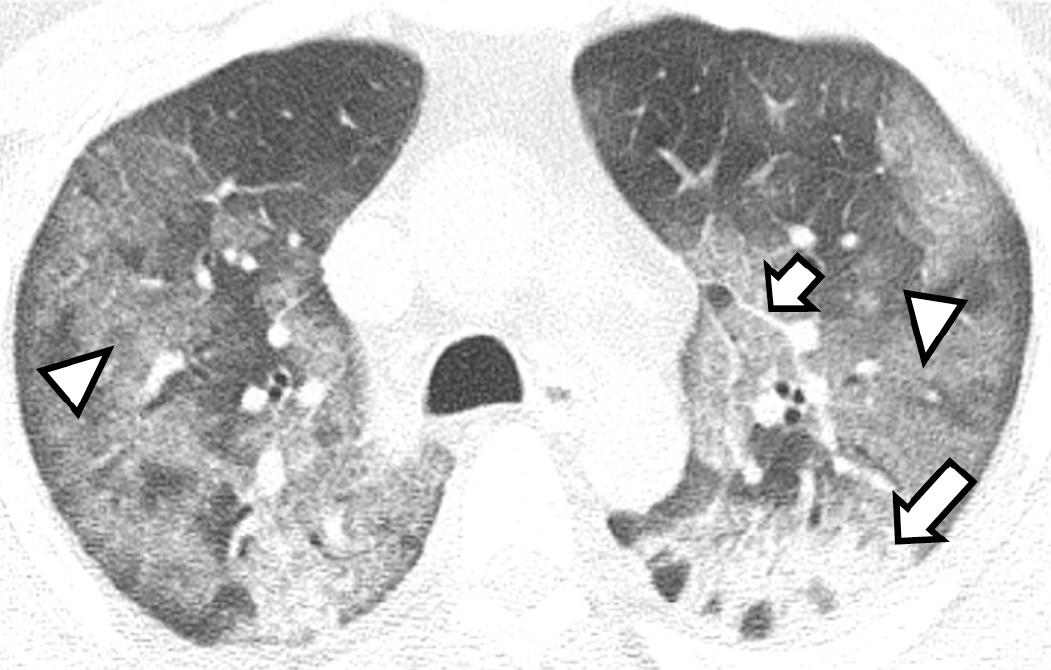

En la tomografía simple de tórax realizada al ingreso de cada paciente, los patrones más comunes fueron los siguientes: opacidad de vidrio esmerilado de predominio periférico y subpleural (Figura 1), encontrado en 15.9 % de los hombres y 20 % de las mujeres; la consolidación, con predominio hacia los segmentos posterobasales (Figura 2); así como los patrones de empedrado y mixto, forma concomitante de los mencionados (Figura 3). En los diagramas de Venn (Figura 4) se representan los porcentajes de las diferentes combinaciones de patrones.

Figura 3 Hombre de 45 años con neumonía causada por SARS-CoV-2, en quien se observa patrón tomográfico mixto. Se aprecian consolidaciones densas en los segmentos posteriores (flecha larga), asociadas a discretos patrones de vidrio esmerilado (punta de flecha) y de empedrado (flecha corta).

Figura 5 Hombre con neumonía causada por SARS-CoV-2 de 10 días de evolución, quien se encuentra en una etapa máxima de la enfermedad. Se observan bandas subpleurales (cabeza de flecha) asociadas a consolidaciones densas (flecha).

–Etapa máxima: el hallazgo más frecuente fue la consolidación densa. En nuestra investigación, los hallazgos incluyeron patrones de vidrio esmerilado, consolidación y empedrado, así como bandas parenquimatosas que causan distorsión de la arquitectura (Figura 5).